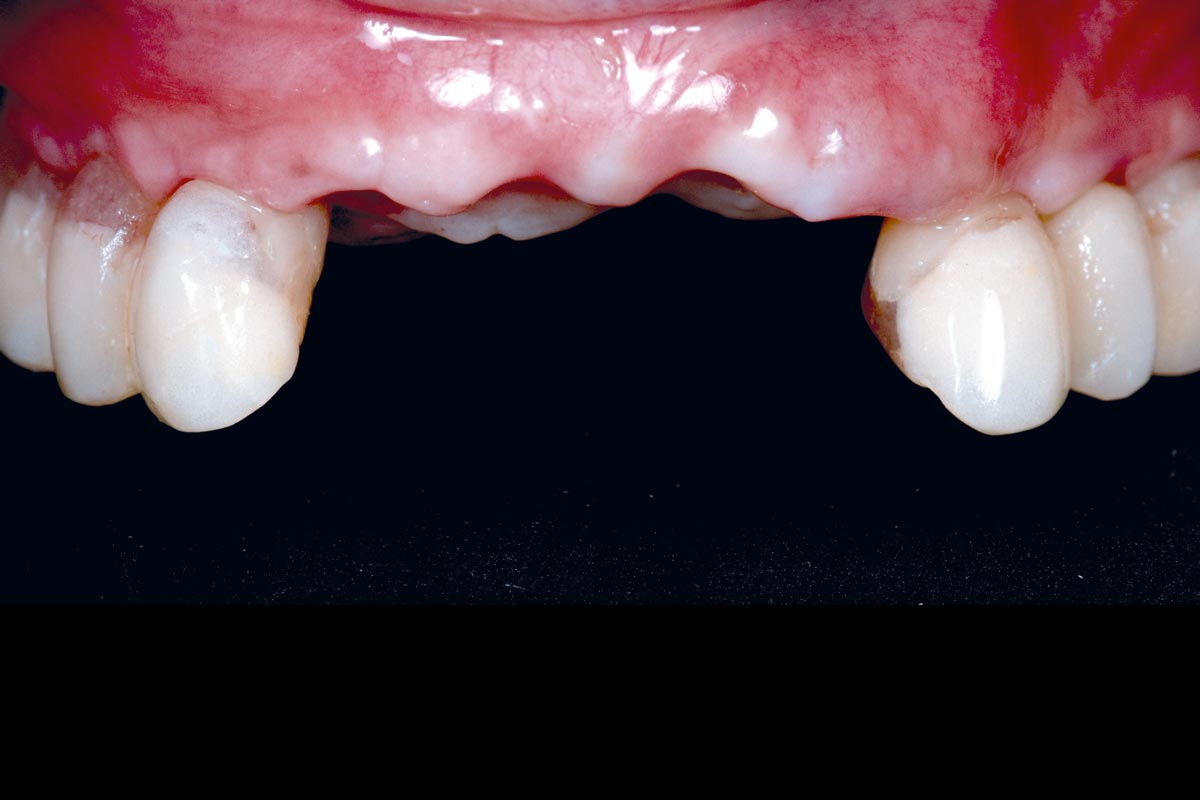

Full arch GBR using cerabone®, maxgraft® and Jason® membrane with simultaneous implantation of 6 Straumann® implants - Dres. A. Signorio and G. Molina